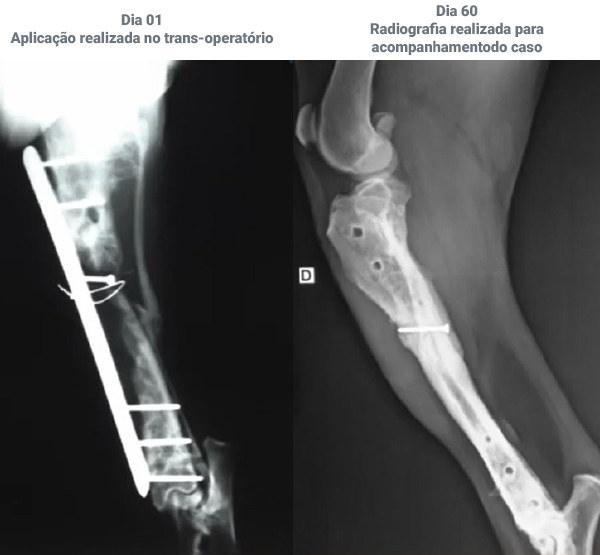

Nada mais é do que um osso que se quebra, na maioria das vezes, em decorrência de um trauma que o animal sofreu. Para realizar o correto diagnóstico da fratura, é necessária a realização de uma radiografia e a partir daí, variando da gravidade da lesão, será feita a escolha do tipo de tratamento podendo variar de uma imobilização até uma cirurgia. Em ambos os casos, o tratamento com células tronco será benéfica.

As células-tronco possuem a capacidade de se diferenciar em osteoblasto, que irá compor a matriz óssea e tem a função de inibir a ação do osteoclasto (célula que promove a reabsorção óssea), diminuindo assim o tempo de consolidação óssea, melhorando a vascularização e diminuindo a inflamação local, levando a formação de um tecido ósseo de melhor qualidade.

A aplicação é realizada no foco da fratura e , na maioria dos casos, não há necessidade de anestesiar o animal.